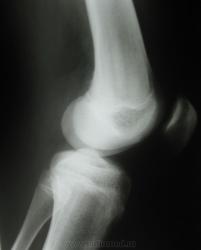

Остеоэпифизеолиз

Молодой человек 17 лет, спортсмен. Неудачное падение на тренировке.

Вот именно это я и хочу - обсудить, как часто подобные изменения видны на рентгене, и видны ли.

Во-во. Грош цена будет нашему методу, если такой перелом не будет виден на рентгенограмме. Разве что нарушить все каноны ее производства.

прямой воще чист, если прицельно разглядывать боковой моооооожет быть + клиника, то что нибудь бы в голове и родилось. интересное наблюдение! Спасибо Евгений!

Я довольно часто, на цифре, поработав с "цифрой", вижу малые травматические изменения, которые на пленочной рентгенограмме не видны.

А мы в равных условиях? МРТ - это цифра, которая доходит на сайт без потери качества. А рентгенограммы, по-моему, аналоговые, могли потеряться детали при оцифровке. Или я не прав?

Метаэпифиз б/б кости выглядит неплохо, а вот то же самое бедренной - отнюдь.

Обработка показала, что "каноны" нарушены.

Конечно же, оцифровка была произведена фотоаппаратом-"мыльницей" с негатоскопа, и качество явно потерялось. Плюс ко всему, исходный снимок...

Я совершенно не силен в обработке изображений, все наугад. Но когда знаеш, где перелом...Короче, вот что плучилось.

Да, исходный пленочный снимок качеством не блещет.

на р-ме большая часть линии перелома перекрывается надколеником, что явно затрудняет её поиски. не думаю что и косые проекции сильно бы помогли. да смещение отломков мизерное.

По всей видимости, "экранная нерезкость", также внесла свою лепту в нивелирование отображения линии перелома.

На снимках в прямой проекции изменен "кортикал" с латеральной стороны........